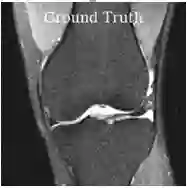

Deep learning based techniques achieve state-of-the-art results in a wide range of image reconstruction tasks like compressed sensing. These methods almost always have hyperparameters, such as the weight coefficients that balance the different terms in the optimized loss function. The typical approach is to train the model for a hyperparameter setting determined with some empirical or theoretical justification. Thus, at inference time, the model can only compute reconstructions corresponding to the pre-determined hyperparameter values. In this work, we present a hypernetwork based approach, called HyperRecon, to train reconstruction models that are agnostic to hyperparameter settings. At inference time, HyperRecon can efficiently produce diverse reconstructions, which would each correspond to different hyperparameter values. In this framework, the user is empowered to select the most useful output(s) based on their own judgement. We demonstrate our method in compressed sensing, super-resolution and denoising tasks, using two large-scale and publicly-available MRI datasets. Our code is available at https://github.com/alanqrwang/hyperrecon.